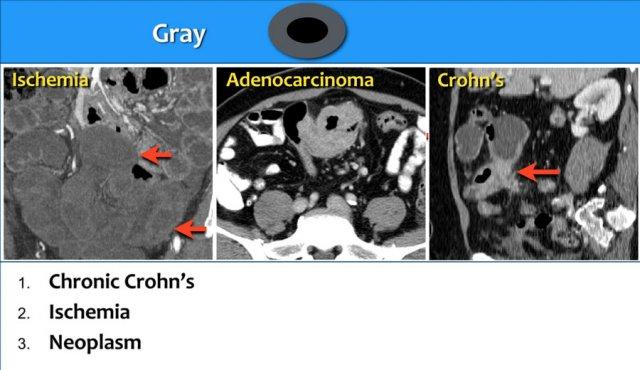

Loại 2 – Tỷ Trọng Xám

Trong kiểu hình tỷ trọng xám, thành ruột dày và mặc dù đã tiêm đủ liều thuốc cản quang, tổn thương vẫn ngấm thuốc kém và không thể phân biệt được các lớp khác nhau của thành ruột.

Kiểu hình này được gặp trong bệnh Crohn mạn tính có xơ hóa, thiếu máu cục bộ và các khối u ác tính như ung thư biểu mô tuyến và u lympho.

Bệnh Crohn mạn tính

Đây là hình ảnh của một bệnh nhân mắc bệnh Crohn mạn tính có hình thành sẹo co rút (cicatrization).

Thiếu máu cục bộ mạc treo ruột

Thiếu máu cục bộ ruột thường ảnh hưởng đến đại tràng và hay gặp nhất ở góc lách, đại tràng xuống và đại tràng sigma.

Nguyên nhân chủ yếu là do tình trạng giảm lưu lượng máu như sốc giảm thể tích hoặc suy tim sung huyết.

Đặc biệt ở người cao tuổi có dày thành ruột, cần luôn đưa thiếu máu cục bộ vào danh sách chẩn đoán phân biệt.